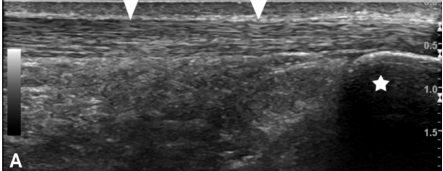

Read more in this article to learn about what it means and what happens when the tendon goes from looking like this:

..to looking like this: